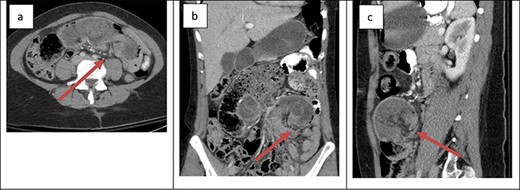

The first patient was a 36-year-old female with a history of type 1 plasminogen activator inhibitor deficiency, open Roux-en-Y gastric bypass 12 years prior, abdominoplasty with bilateral breast augmentation and chronic abdominal and back pain. She was 275 lbs at the time of her gastric bypass and 165 lbs at the time of presentation. The patient presented with a short history of new abdominal pain after a recent meal. No other associated symptoms were present upon presentation. Her vitals were within the normal limits and laboratory work was unremarkable. An abdominal ultrasound was obtained to evaluate for biliary disease, which revealed cholelithiasis without further evidence of acute process. Cross-sectional imaging revealed a small bowel obstruction secondary to small bowel intussusception at the jejunojejunal anastomosis (Fig. 1). The patient was taken emergently to the operating room for a laparoscopic lysis of adhesions and reduction of intussusception. In the operating room, ~60 cm of jejunum was found to be involved at the site of the jejunojejunostomy; after reduction, the involved bowel appeared viable so no formal resection or revision was performed. The patient’s post-operative course was uncomplicated. She was started on clear liquids on POD#1 and discharged home on POD#4. After discharge, the patient continued to experience episodic pain consistent with her chronic abdominal pain. Cross-sectional imaging ruled out further episodes of intussusception.

Cross-sectional imaging of displaying bowel and mesentery (arrow) intussuscepting into the JJ anastomosis on (a) transverse view, (b) coronal view and (c) sagittal view.

The presentation of intussusception is widely variable depending on the severity of the disease process. Common presentations include abdominal pain, nausea and vomiting, new palpable abdominal mass, lower GI bleeding and signs of sepsis. Intussusception can be diagnosed through various imaging modalities such as cross-sectional imaging, plain radiographs, small bowel series and ultrasonography. Cross-sectional imaging is believed to be not only highly sensitive but also reliable [3]. On cross-sectional imaging, intussusception appears as a complex soft tissue mass representing bowel telescoped onto itself often with an eccentric area of hypoattenuation within the mass representing the intussuscepted mesenteric fat [5]. The pathognomonic appearance is appreciated in Figs 1 and 2. Furthermore, the wall of the internalized loop of bowel can be observed within the dilated bowel when imaging is enhanced with intravenous contrast. Prompt diagnosis and surgical intervention are paramount in management of intussusception.